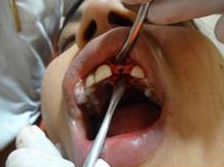

Punch Cut

Placement of Bone Grafting

After Punch Cut

Drilling for Implant